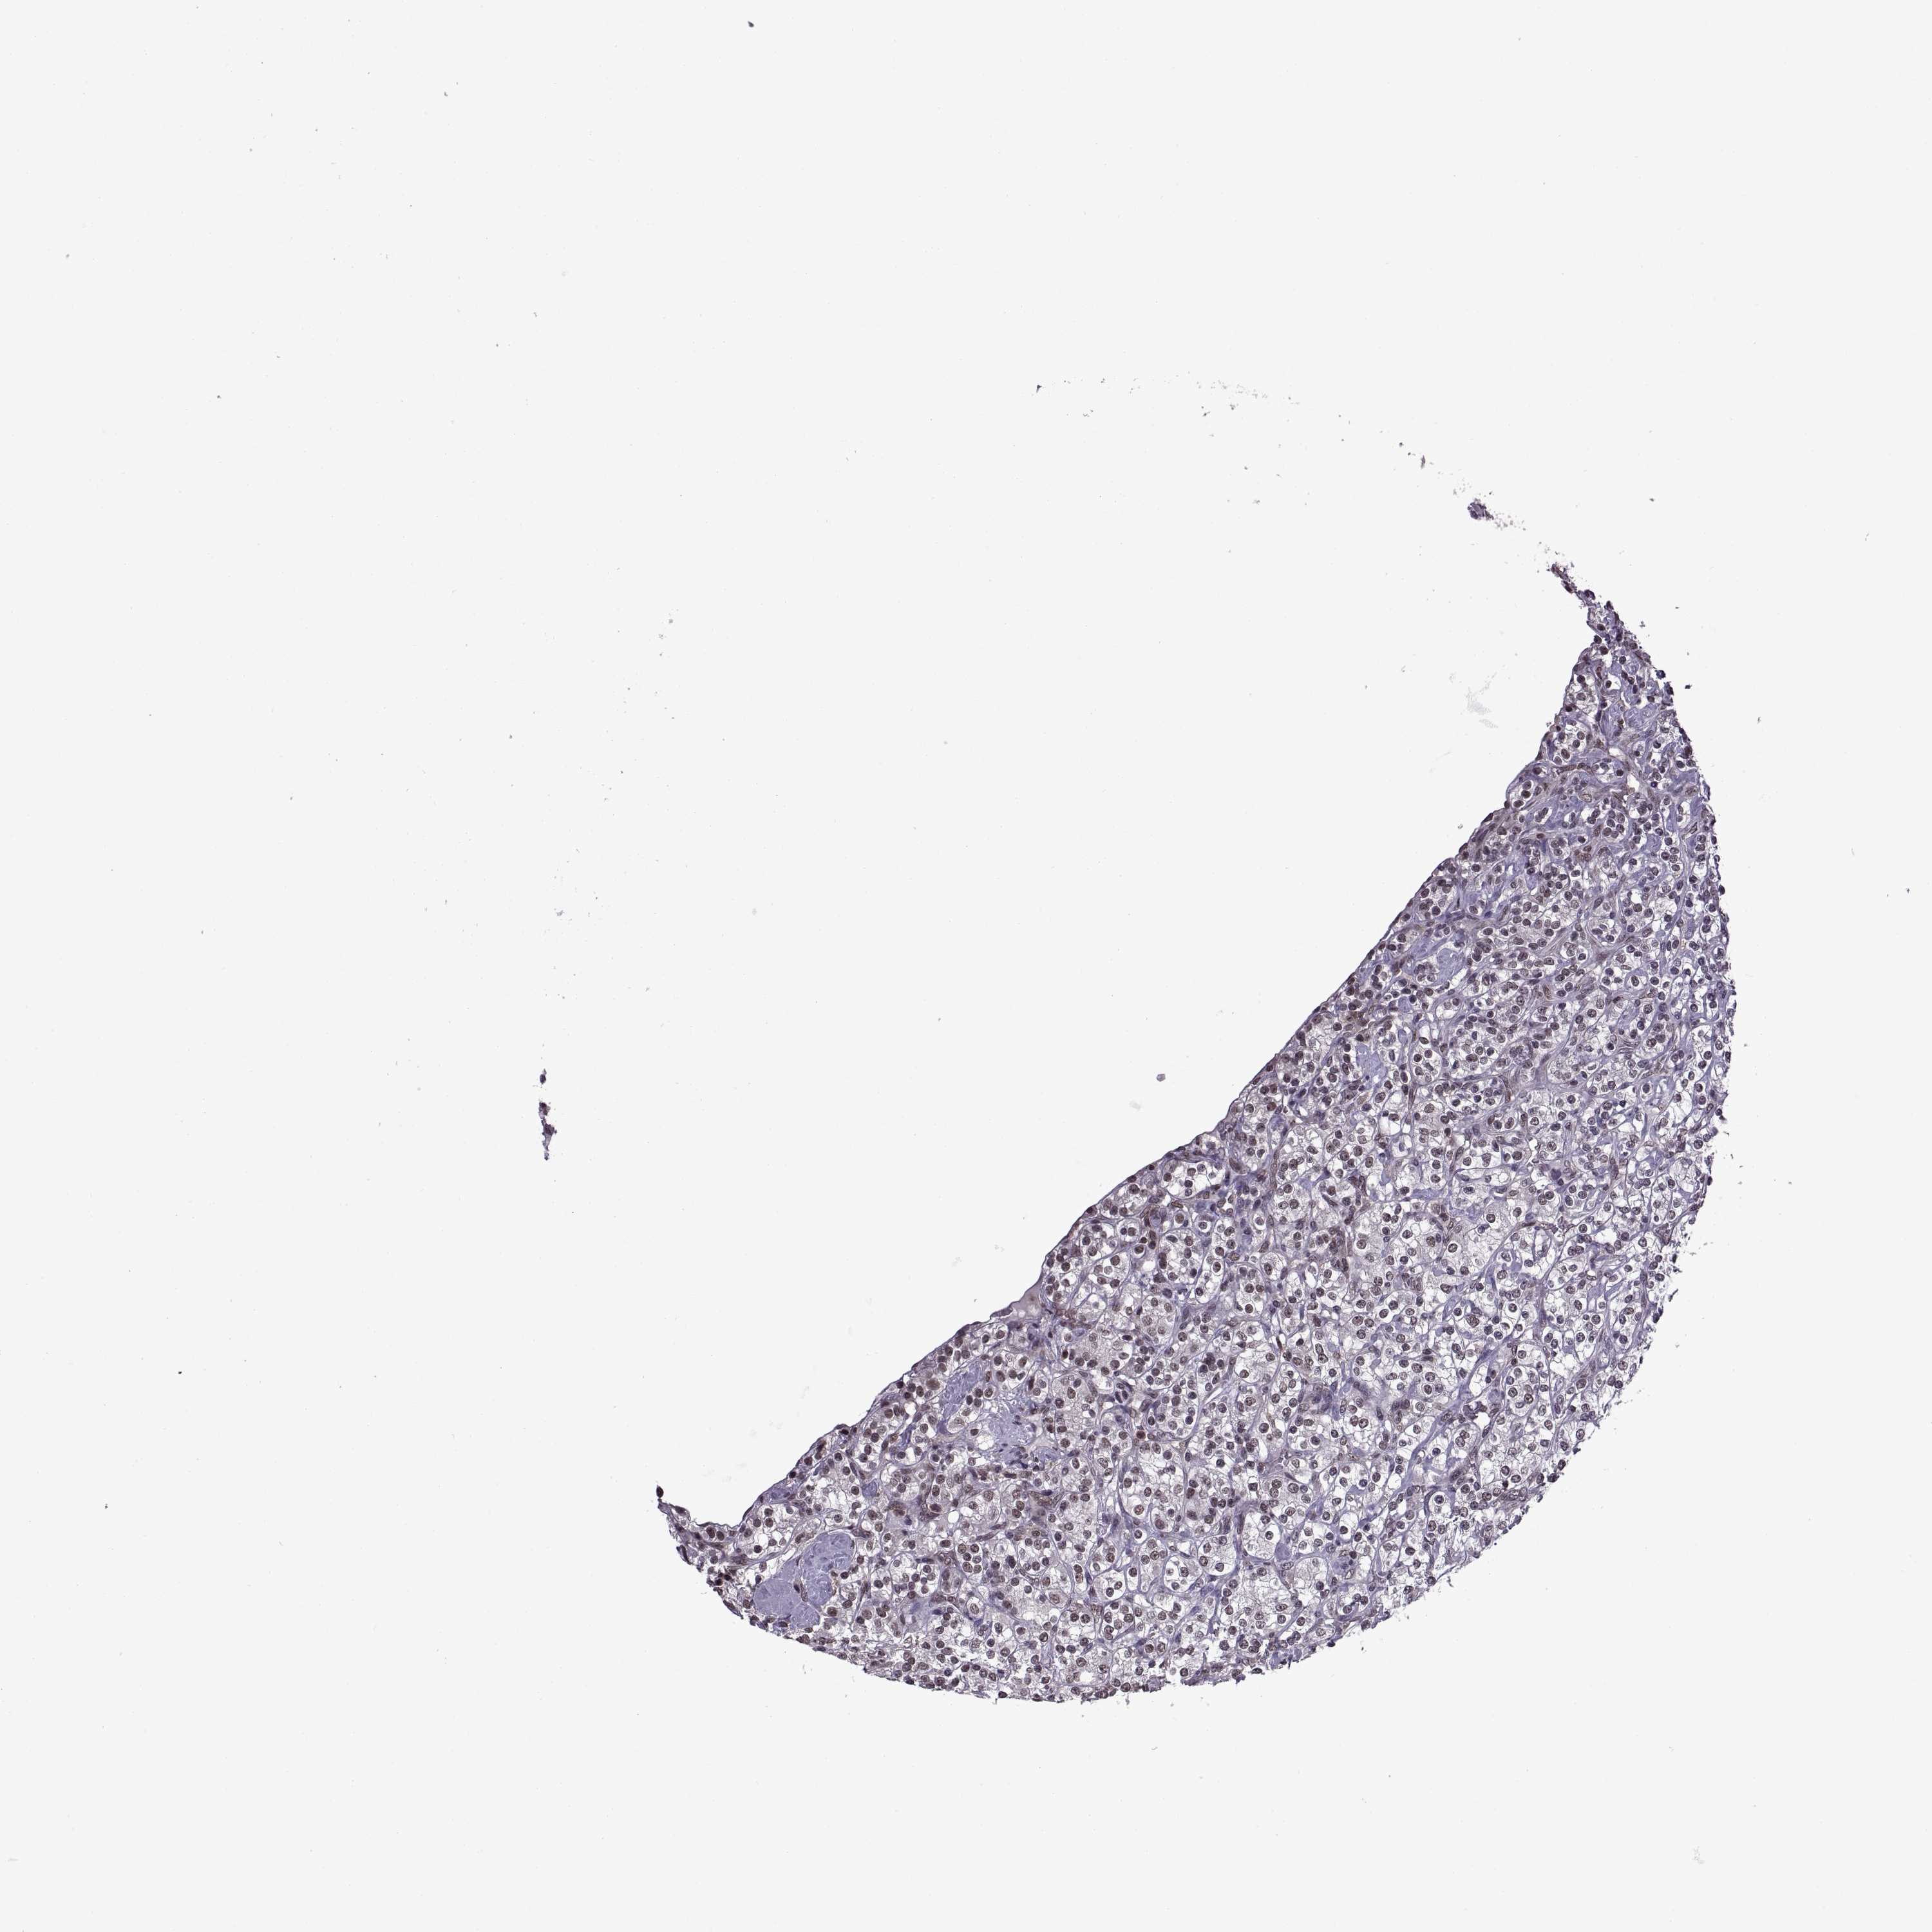

Renal cancer

Kidney chromophobe

KIDNEY CHROMOPHOBE (TCGA) - Interactive survival scatter ploti

INTS3 is not prognostic in Kidney Chromophobe (TCGA)